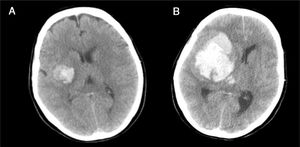

Caso 2Mujer de 65 años con antecedentes de HTA y cardiopatía isquémica en tratamiento con antiagregantes y antihipertensivos. Hemiplejia izquierda y disartria con un GCS de 14. En la TC craneal se evidencia pequeña hemorragia derecha en los ganglios de la base (fig. 5A), por lo que ingresa en la unidad de ictus para control. A las 4h presenta crisis hipertensiva, deterioro del nivel de consciencia con un GCS de 6 (O1-V1-M4) y anisocoria con midriasis derecha arreactiva. En una nueva TC se observa hemorragia masiva hemisférica derecha (fig. 5B), con signos de herniación subfalcial. Ingresa en la UCI y, dada la gravedad de la lesión, se descarta cualquier tipo de tratamiento. Se informa a la familia y al CT, quien comprueba que la paciente contaba con documento de instrucciones previas en el que manifestaba su deseo de ser donante de órganos, hecho que es comunicado a la familia, quien acepta continuar con CIOD y cumplir la voluntad de la paciente. A las 15h de su ingreso se confirma la ME. Donante de hígado y 2 riñones, que fueron trasplantados con resultado satisfactorio.